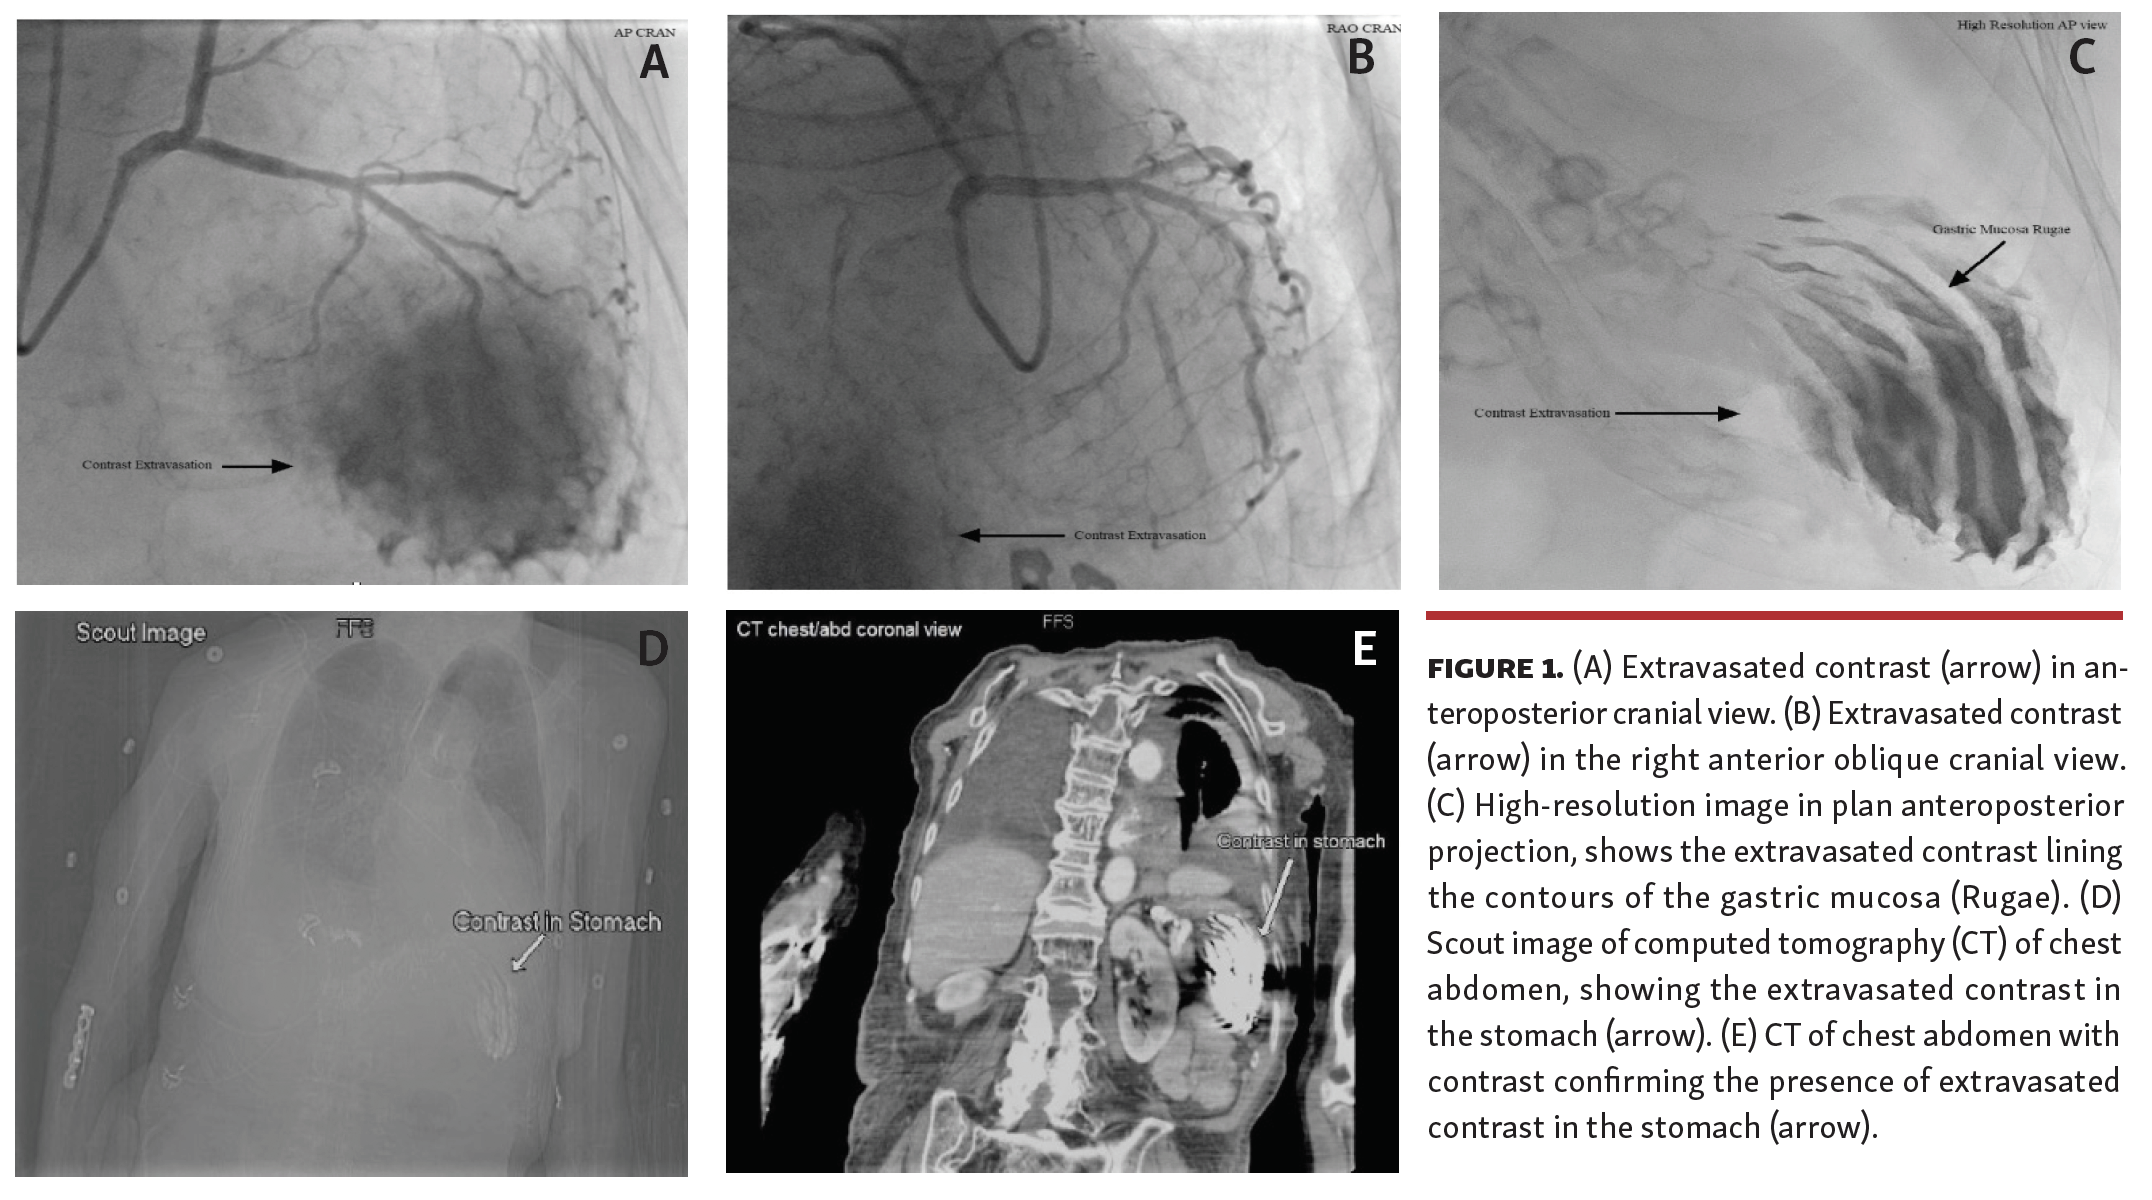

A 79-year-old woman presented with new-onset heart failure. She had pleural effusion, pericardial effusion, and an ejection fraction of 35% on echocardiogram. Her coronary angiogram revealed mild coronary artery disease (CAD). However, initially unexplained extravasation of the contrast was also seen in the cranial view during angiogram (Figures 1A and 1B). The decision was made to medically manage CAD, but she remained tachycardic, with borderline low blood pressure. A few hours later, she was taken back to the lab for pericardiocentesis, which drained only 20 mL of clear fluid. High-resolution fluoroscopic images showed an unusual and unexplained appearance of the contrast again, possibly in a subdiaphragmatic location (Figure 1C). She then developed melena. Computed tomography (CT) of the chest and abdomen with intravenous contrast confirmed the extravasated contrast concentrated in the stomach (Figures 1D and 1E). Endoscopy also showed the Cameron erosions in the hiatal hernia and “coffee ground” material in the stomach. Follow-up CT with contrast following stabilization of the patient confirmed the clearance of contrast from the stomach. This represents an unusual case in which fluoroscopy revealed active gastric bleeding with contrast extravasation during coronary angiography.